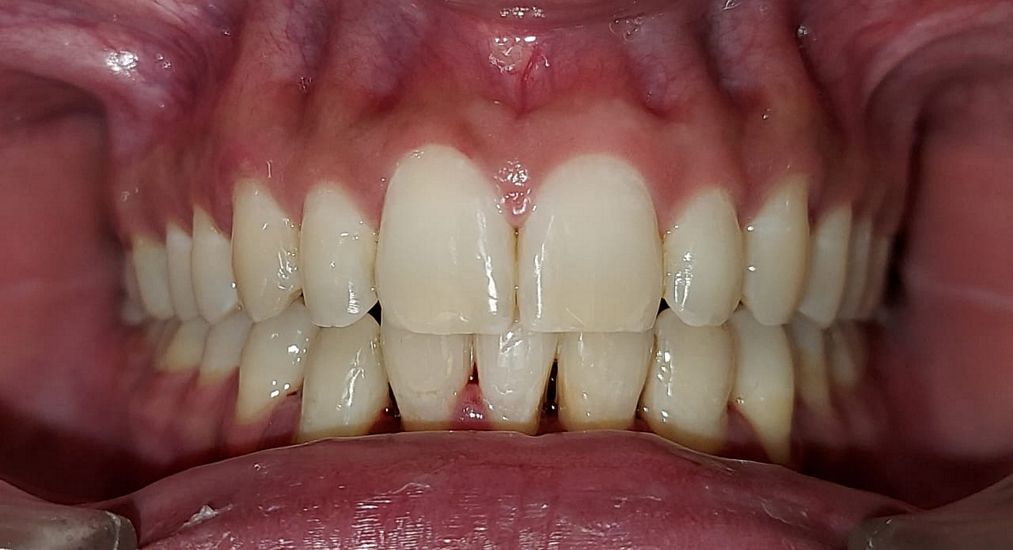

Case No: 22

Malocclusion Type: Class I Malocclusion.

Mechanics: MBT Mechanics.

Treatment: Class I Malocclusion with crowding in upper and lower anteriors treated by Non-extraction (permanent teeth)method.